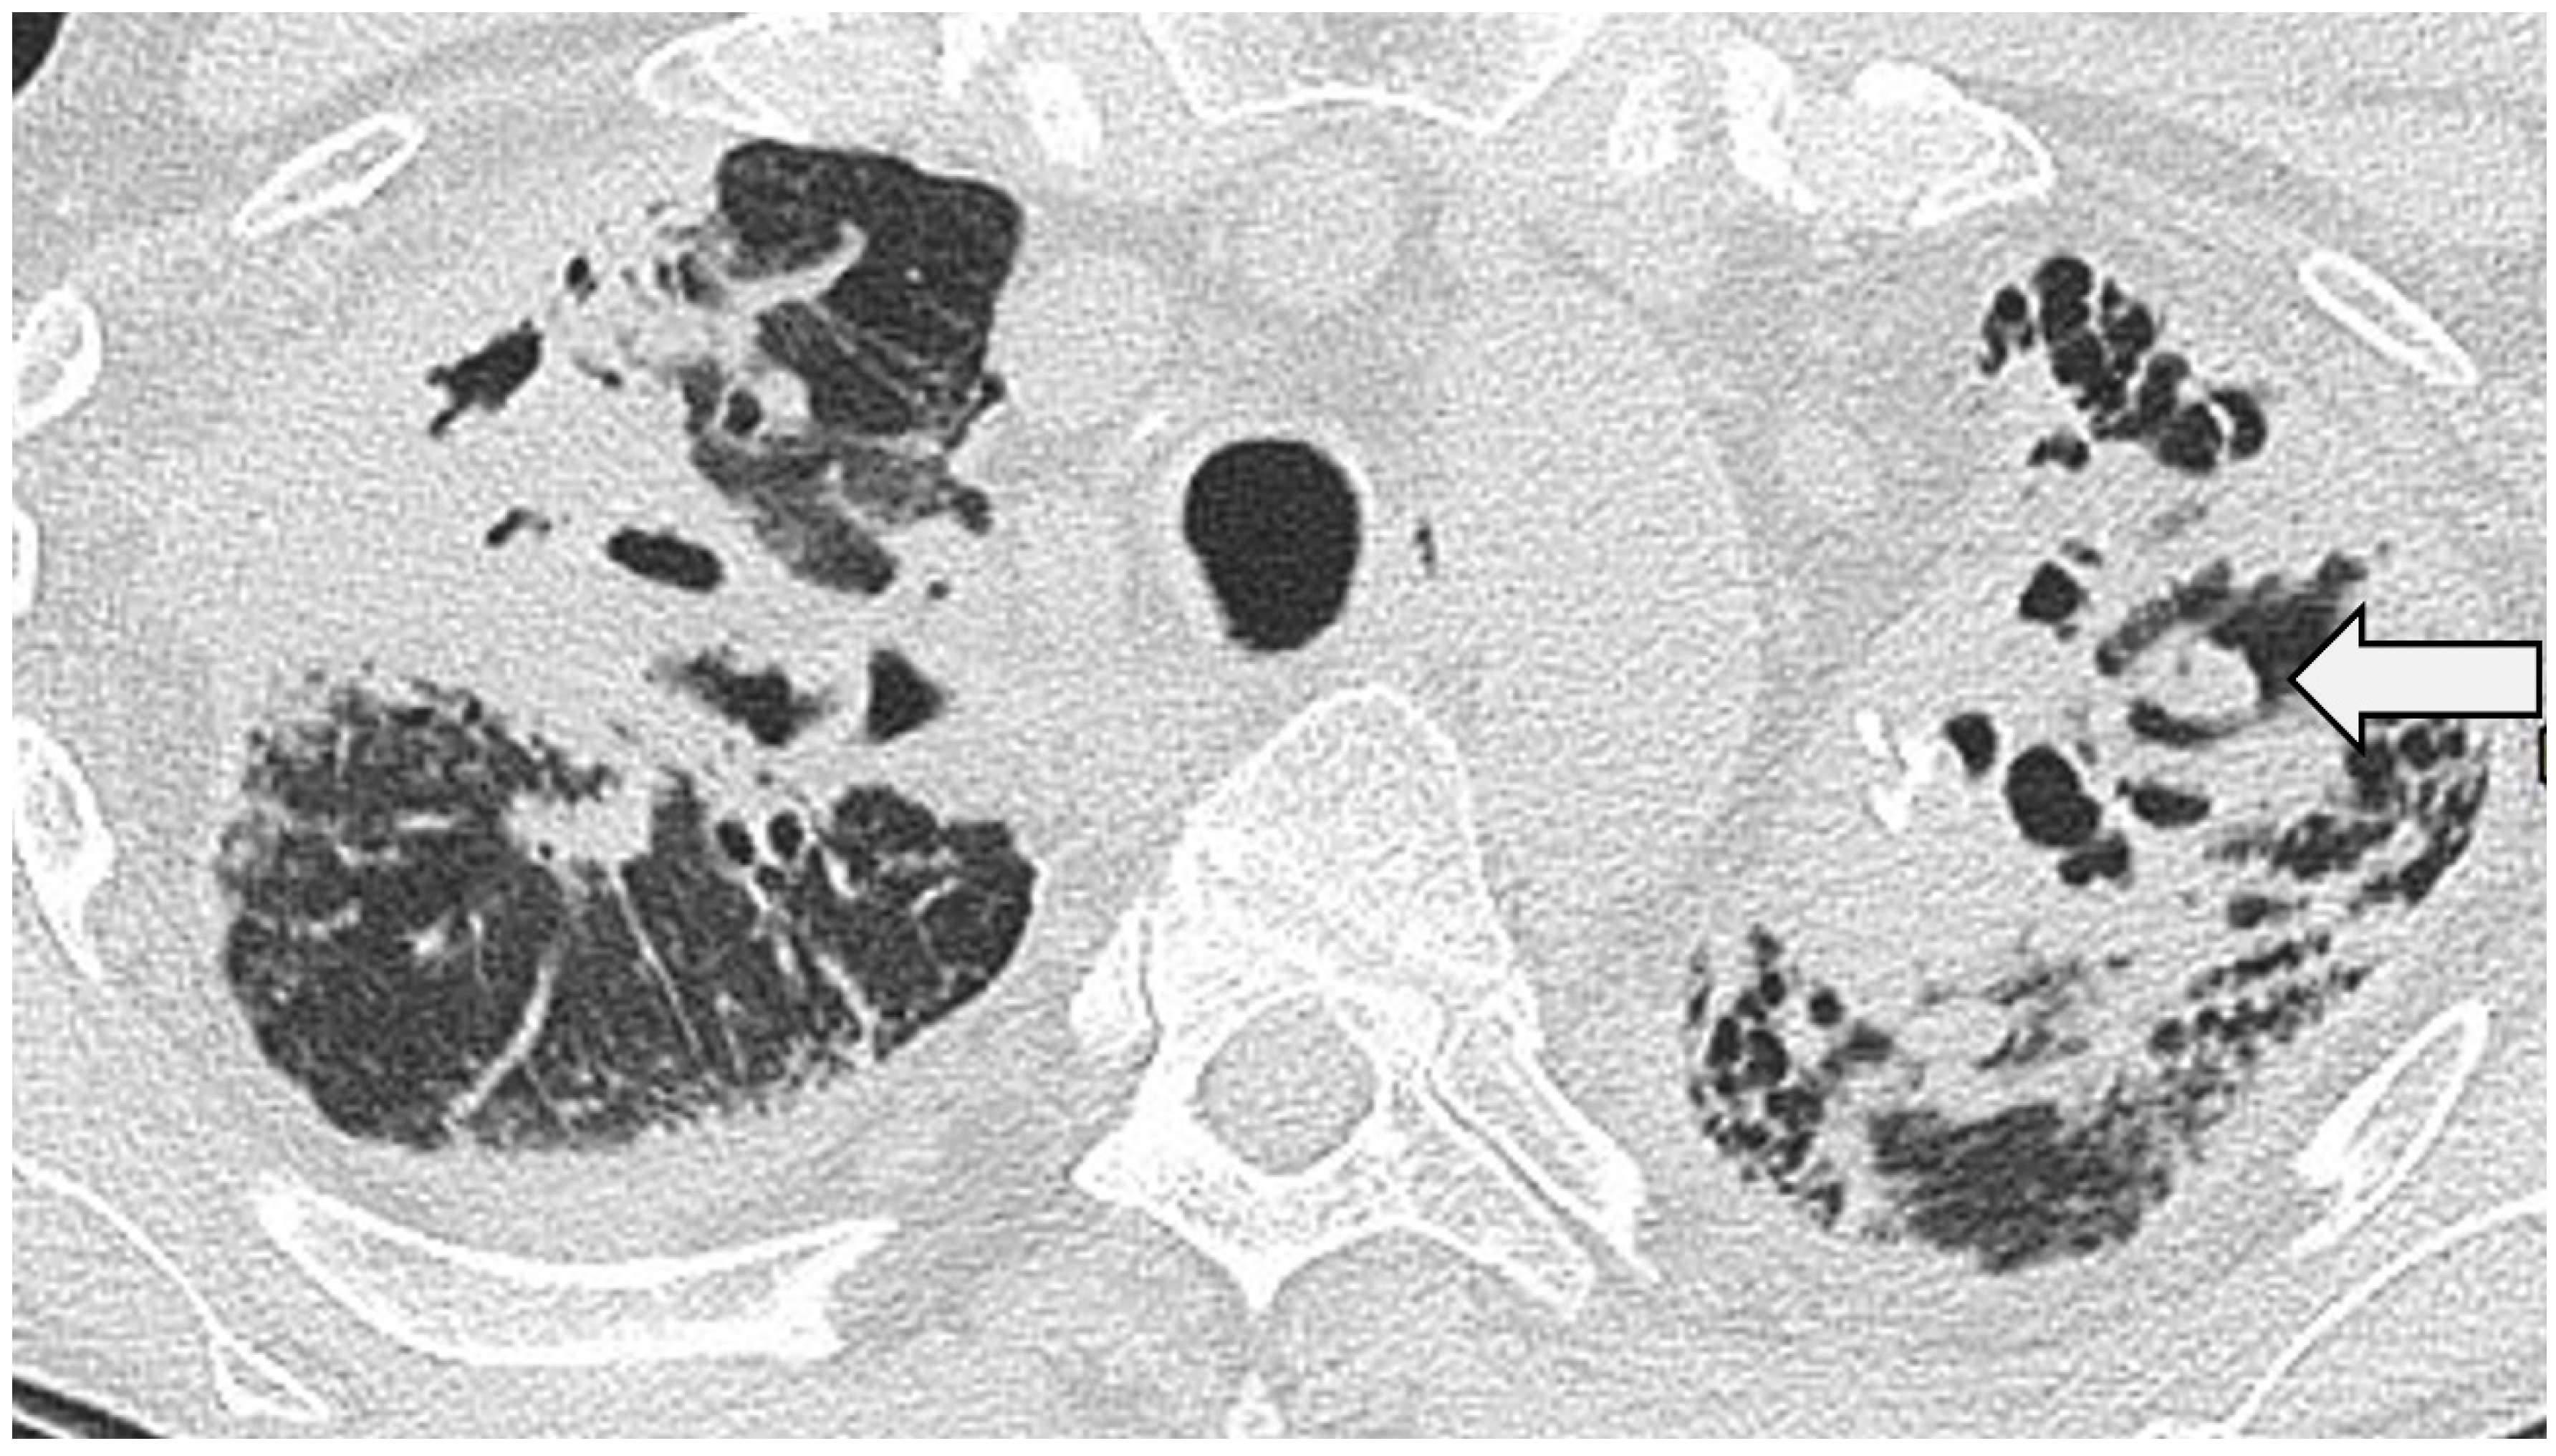

Clustering of micronodules around a larger central nodule gives rise to the so-called ‘galaxy sign’ [62], (Figure 3) reportedly seen in nearly one-third of patients [63], but not pathognomonic for sarcoidosis [64].

Nodular sarcoidosis in a 46-year-old male patient. CT at the level of the aortic arch showing large nodules with surrounding micronodules (the ‘galaxy sign’) in both upper lobes (arrows).